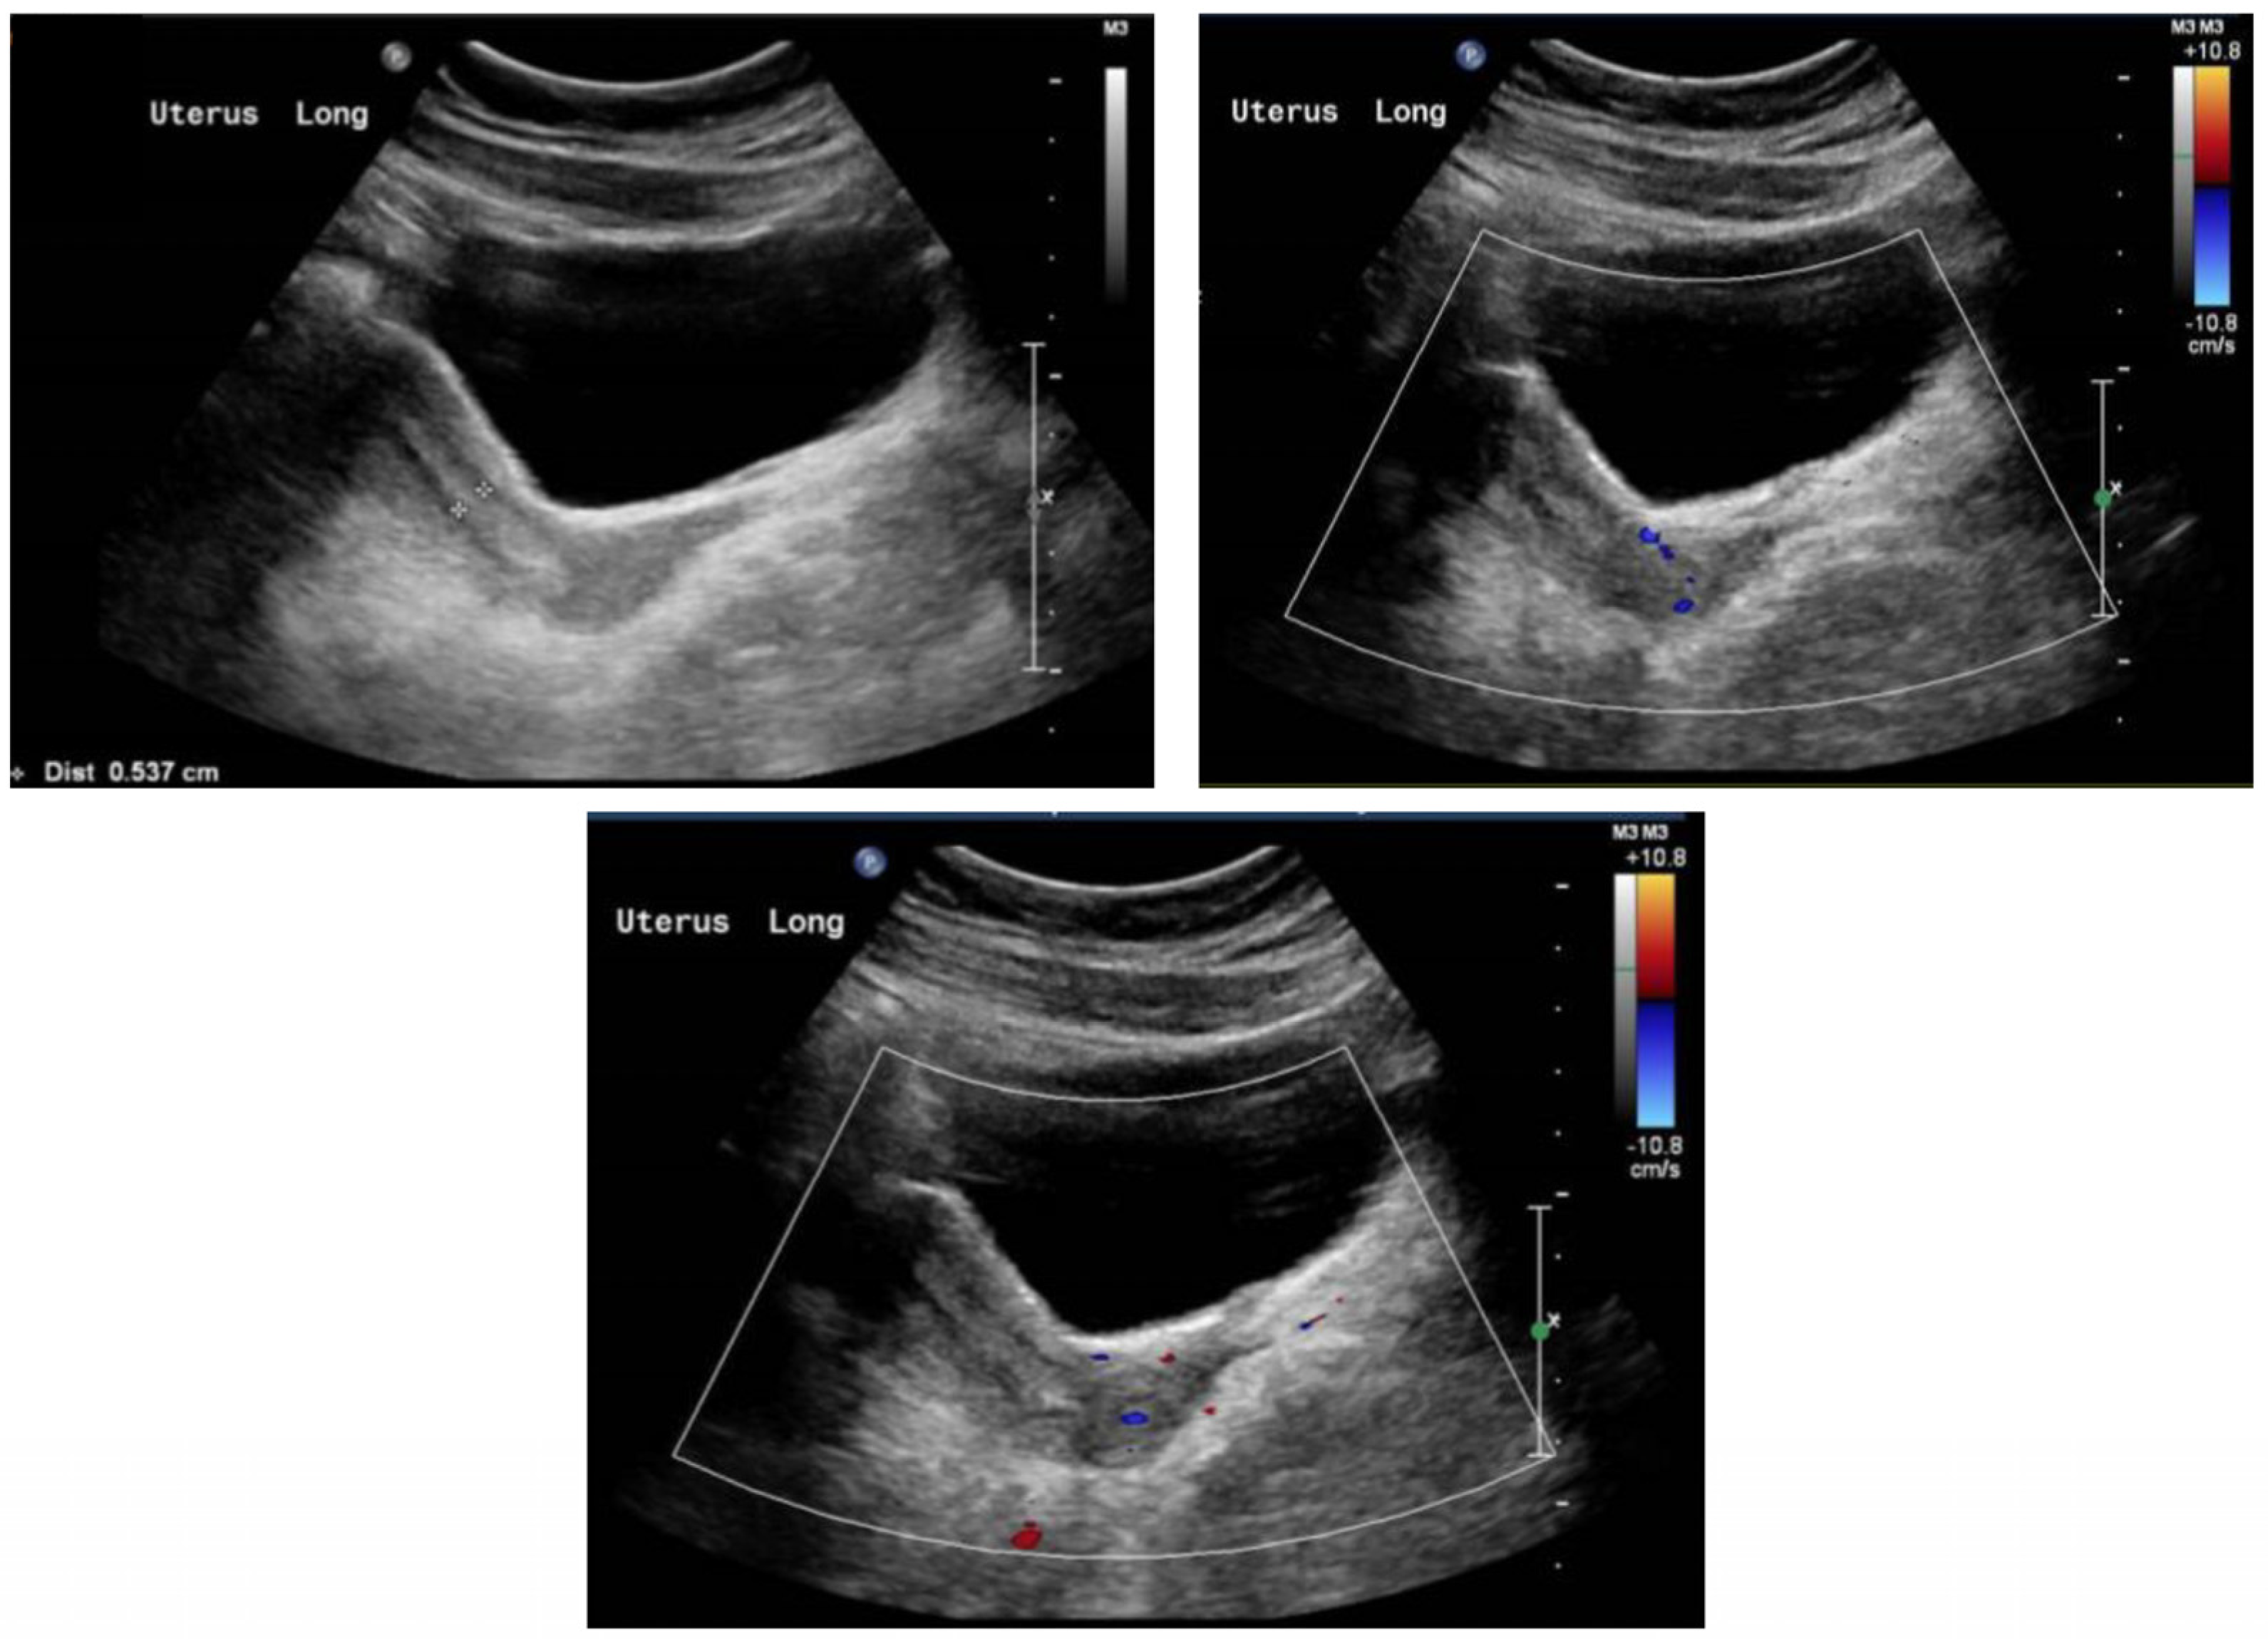

2. Case Report